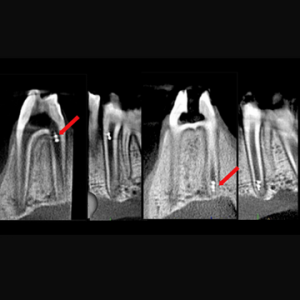

En 2004, se introdujo una nueva técnica para el tratamiento de dientes inmaduros no vitales, denominada procedimiento de endodoncia regenerativa (REP, también conocido como revascularización), que...